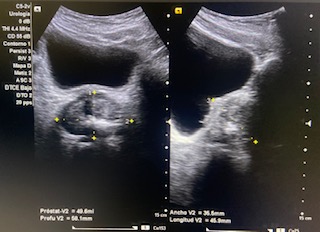

Volumen residual: 243 ml. Próstata de contornos regulares y ecogenicidad homogénea a simple vista. Volumen prostático: 49 cc.

En ecografía determinamos el tamaño de la próstata mayor de 20 cc, por tanto se trata de una HBP grado II. La medición del RPM nos permitió detectar que el paciente presentaba residuos elevados (243 ml).